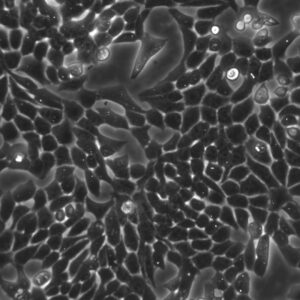

Morphology: Epithelial-like

Growth Properties: Adherent

Description: HuH7 was established in 1982 by Nakabayashi et al. from a 57-year-old Japanese male with well differentiated hepatocellular carcinoma.